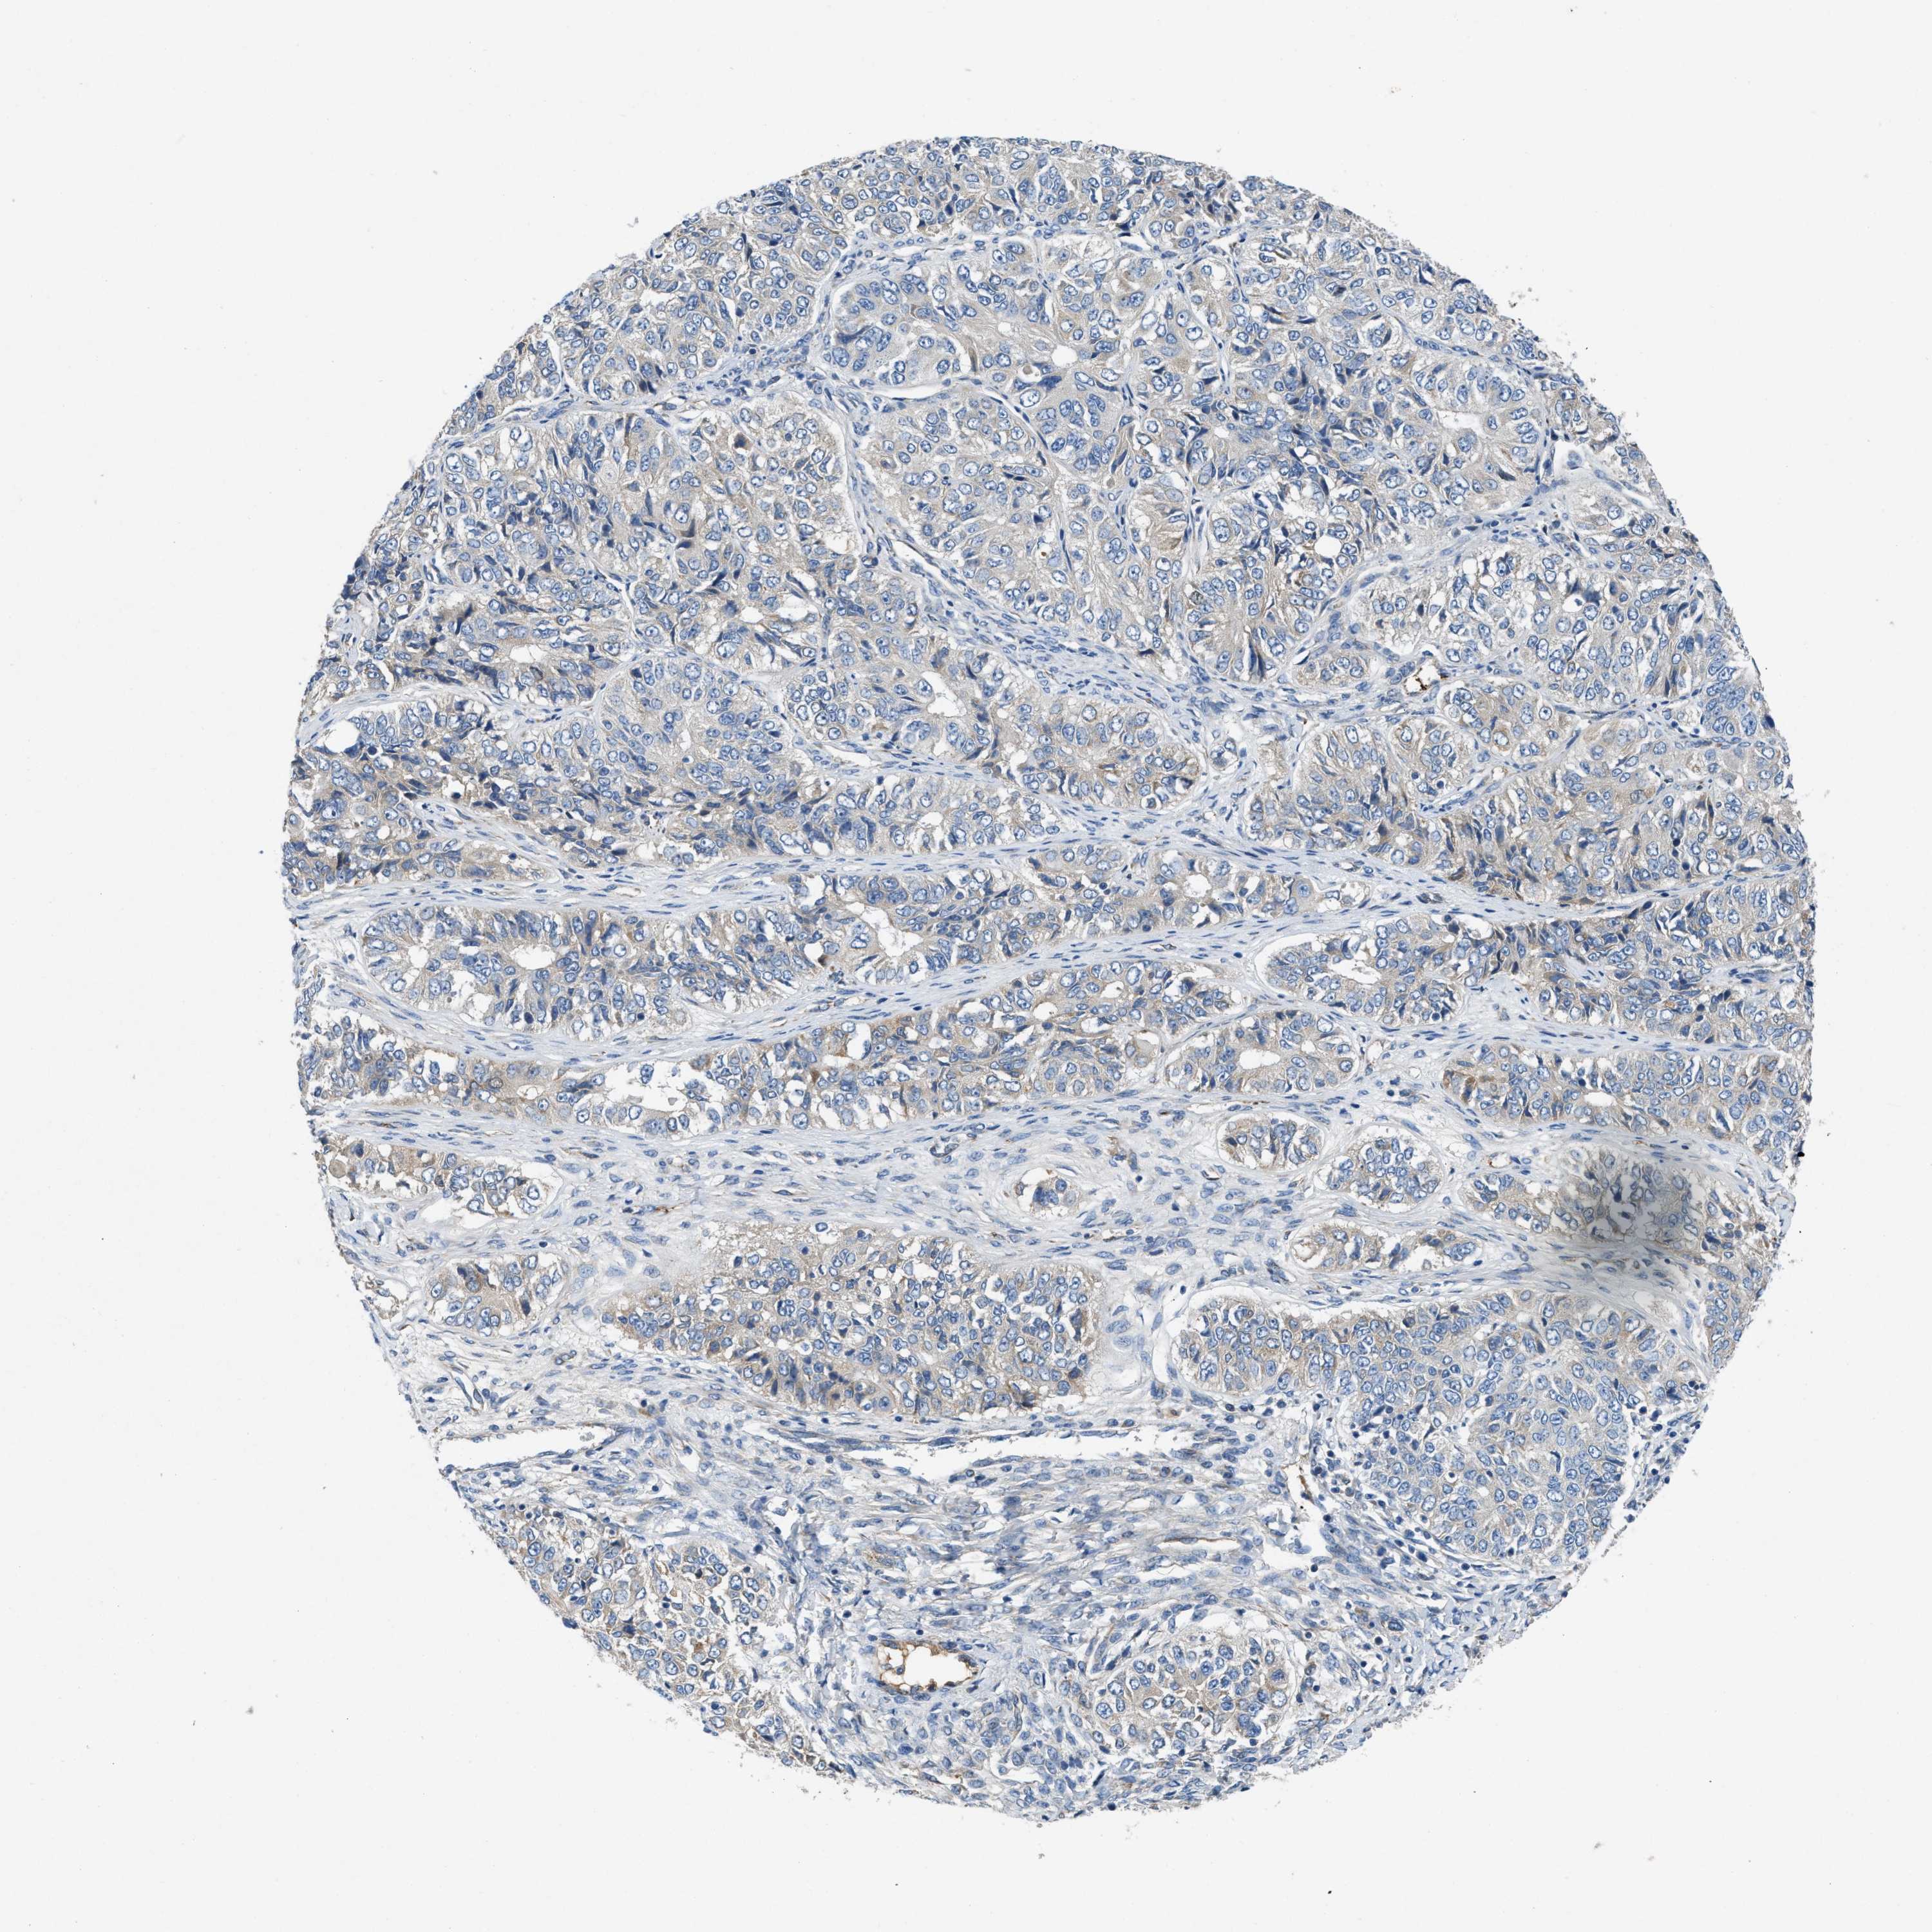

OVARIAN CANCER - Protein expressioni

A mouse-over function shows sample information and annotation data. Click on an image to view it in a full screen mode. Samples can be filtered based on level of antibody staining by selecting one or several of the following categories: high, medium, low and not detected. The assay and annotation is described here.

Note that samples used for immunohistochemistry by the Human Protein Atlas do not correspond to samples in the TCGA dataset.

Antibody stainingi

Antibody staining in the annotated cell types in the current human tissue is reported as not detected, low, medium, or high, based on conventional immunohistochemistry profiling in selected tissues. This score is based on the combination of the staining intensity and fraction of stained cells.

Each image is clickable and will lead to virtual microscopy that enables deeper exploration of all samples and also displays staining intensity scores, fraction scores and subcellular localization as well as patient and tissue information for each sample.

Antibody HPA018284

Staining

High

Medium

Low

Not detected

Intensity

Strong

Moderate

Weak

Negative

Quantity

>75%

75%-25%

<25%

None

Location

Nuclear

Cytoplasmic/membranous

Cytoplasmic/membranous,nuclear

Cystadenocarcinoma, serous, NOS

Carcinoma, endometroid

Cystadenocarcinoma, mucinous, NOS

Carcinoma, NOS